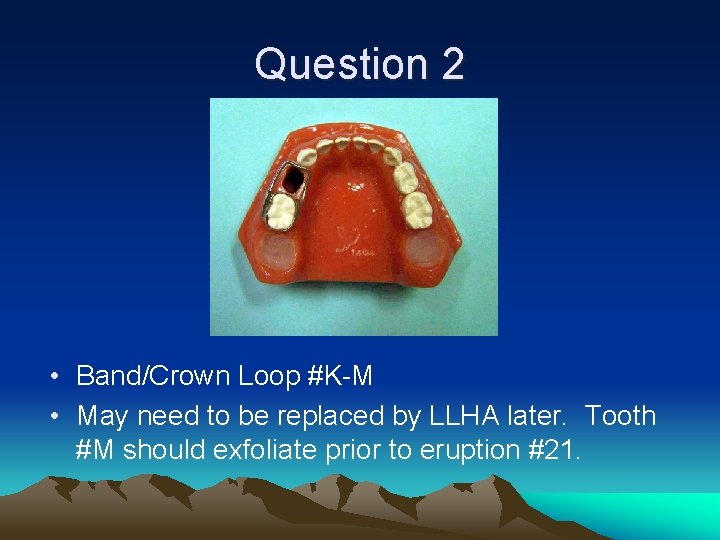

Question 2 • Tooth #L extracted. 3 -5 y. o. child. • What is the appropriate space maintainer? • Will it have to be replaced with a different space maintainer in the future? If so, with what?

Question 2 • Band/Crown Loop #K-M • May need to be replaced by LLHA later. Tooth #M should exfoliate prior to eruption #21.